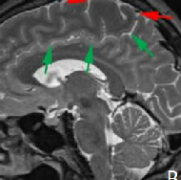

四脑室肿瘤手术风险大吗?图解四脑室肿瘤手术策略

由于四脑室肿瘤与脑干的关系变异程度较大,从简单推挤浸润脑干,因此,尽管相对于三脑室肿瘤而言手术难度较低,切除四脑室肿瘤对外科医生来说仍然是一个挑战。由于肿瘤经常为...